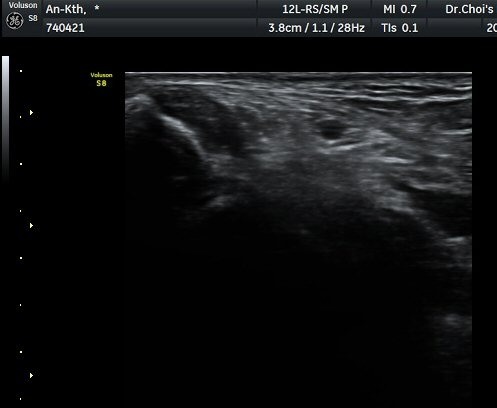

°üÂûµÈ´Ù(±×¸² 1, 2, 3). ±ä¾öÀÚ±¼°î°Ç Á¾´Ü¸é°Ë»ç¿¡¼­ ±ä¾öÁö±¼°î°ÇÀÇ ºÎÁ¾°ú

°Ç ½ÉºÎ¿¡ ¼ö¾×Àú·ù°¡ °üÂûµÊ(±×¸² 4).